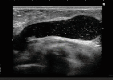

THE CLINICではそんな問題を完治すべく、最先端のエコーを導入して治療にあたっています。